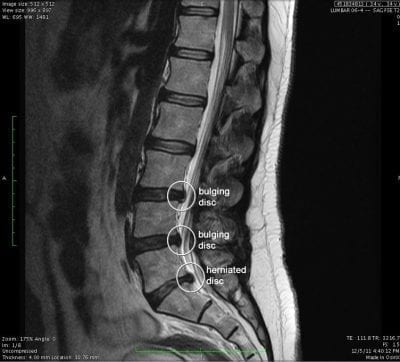

- Disc budges refer to a spinal injury, that can occur in the cervical (neck), thoracic (midback) or lumbar (lower back).

- The disc is described the same way as a fluid filled sac in between each intervertebral joint, that has an outer part (annulus fibrosis) and an inner part (nucleus propolsus).

- The issue with having a disc bulge is when they bulge, and protrude backwards, and pinch the spinal nerves on the left or ride sides of the back, running out of the intervertebral foraminae.

- When the nerves are pinched by the produding disc, they cause inflammation and irritation, and therefore the patient will report symptoms such as weakness in leg muscles, especially during walking, sharp shooting radiating pain down the left leg, and pins and needles